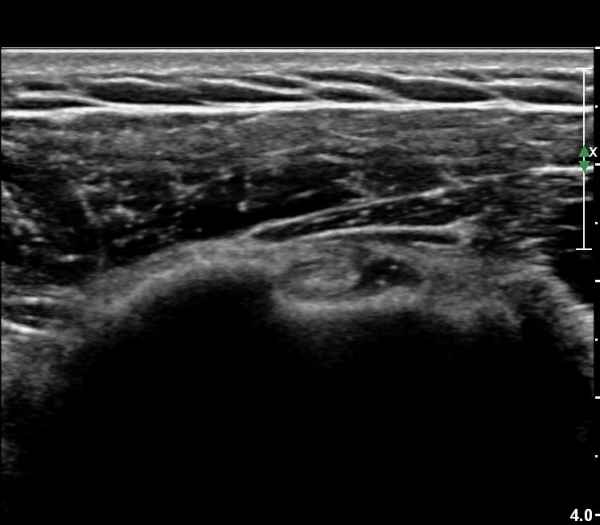

¾î±ú¸¦ ³»Àü, ³»È¸ÀüÇÑ »óÅ¿¡¼­ ±Ø»ó°ÇÁ¾´Ü¸é°Ë»ç»ó  ³»ÃøºÎ ÆÄ¿­ÀÌ °üÂûµÇ°í»çÁø 6, 7)

Ⱦ´Ü¸é°Ë»ç¿¡¼­ ±Ø»ó°Ç ³»ÃøºÎ ÆÄ¿­°ú ºÎÁ¾ÀÌ °üÂûµÈ´Ù(»çÁø 8), ŽÃËÀÚ¸¦ ¸»´ÜÀ¸·Î À̵¿ÇÏ´Ï

±Ø»ó°Ç ºÎÂøºÎ ÆÄ¿­ÀÌ ¶Ñ·ÈÇÏ´Ù(»çÁø 9).